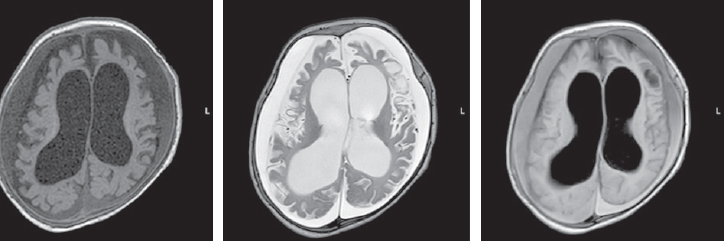

At the age of three months, an MRI of the brain revealed symptoms of delayed myelination, including an increase in the magnetic resonance signal of the posterior parts of the globus pallidus on both sides (Fig. 2).

Fig. 2. Magnetic resonance imaging of a patient at the age of 3 months. Axial sections, T1 VI, T2 VI, Flair. The signs of delayed myelination, were found to be symmetrical at the level of the perirolandic region. The architectonics of the furrows and convolutions have not been changed

Рис. 2. Магнитно-резонансная томограмма пациента в возрасте 3 мес. Аксиальные срезы, Т1ВИ, Т2 ВИ, Flair. Выявлены признаки задержки миелинизации, симметричные на уровне перироландической области. Архитектоника борозд и извилин не изменена